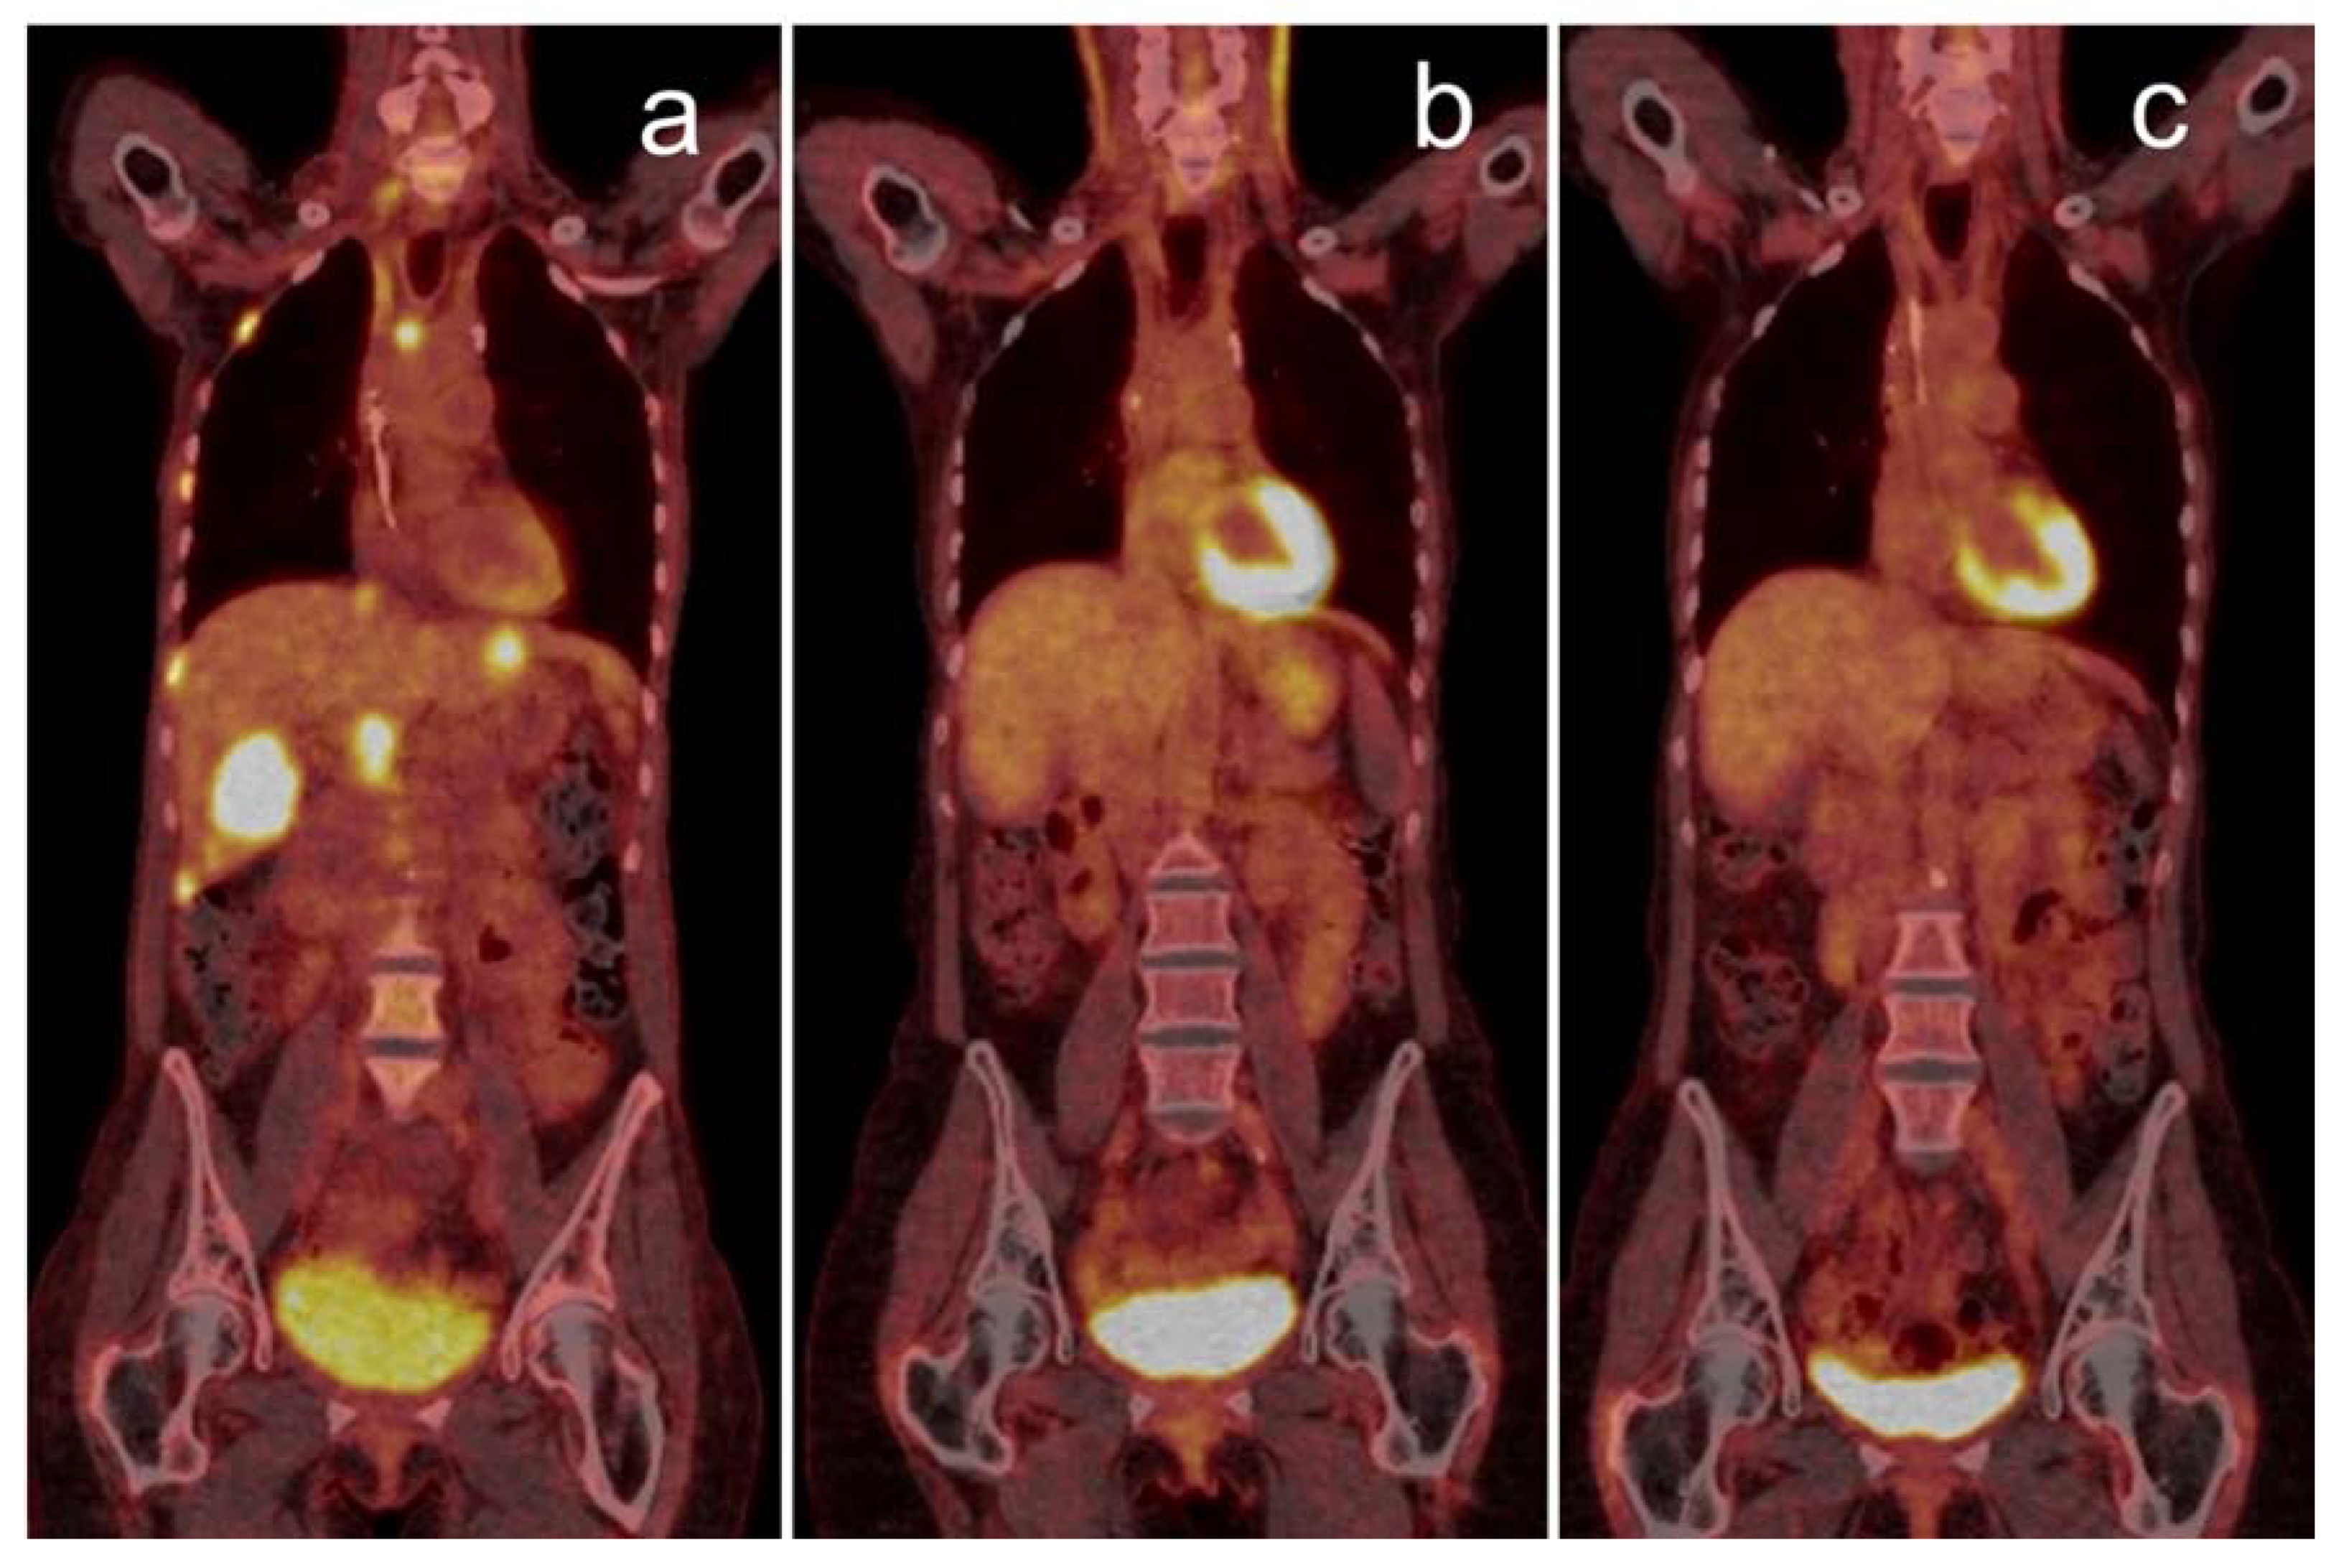

264_2021_5218_Fig3_HTML.png

264_2021_5218_Fig3_HTML.png